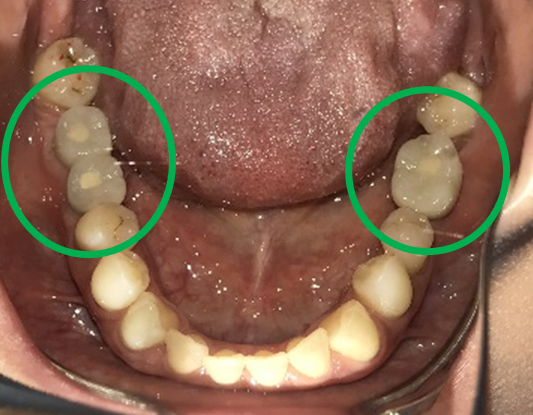

女性Mさん 40代(インプラント)

主訴

下、左右歯がないところに歯を入れたい。

治療内容

右下に2本、左下に1本インプラントを入れました。

所感

下顎左右奥の歯がないところに、インプラント治療を希望されて来院されました。X-Guideを使用し埋入しました。治療後「左右の奥歯でしっかり噛めてうれしいです。」と、とても喜んでくださいました。

インプラント3本:¥363,000×3本=¥1,089,000(税込)

Before

After